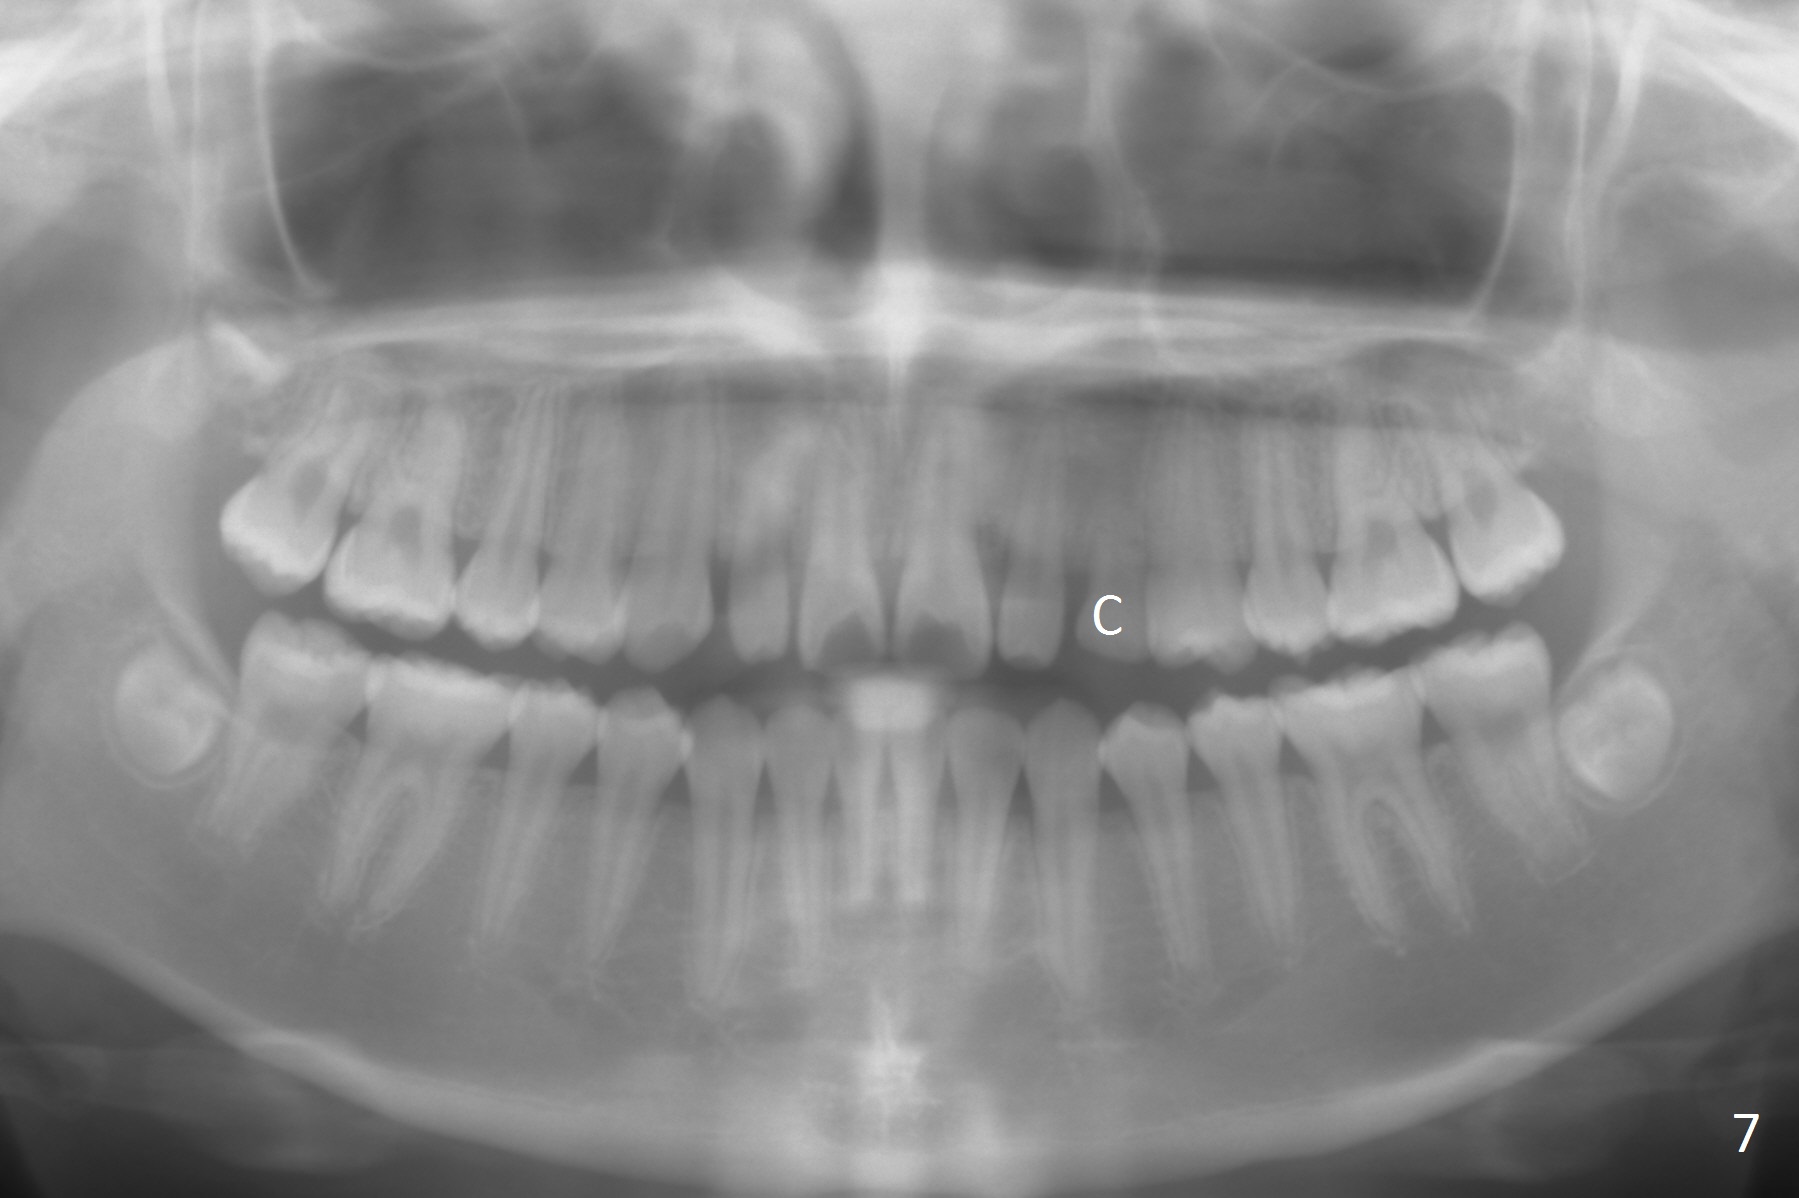

Two sisters (Sophia, 13 years old and Selina, 11) present to clinic for orthodontic treatment. Dental anomalies of Sophia include microdontia of the upper lateral incisors and congenital missing of the upper right permanent canine (Fig.5,6). For Selina, the upper right lateral incisor (Fig.5') and the upper left second bicuspid (Fig,6') are in cross bite.